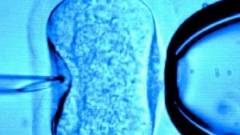

The use of an IVF technique involving DNA from three people to create a baby has moved a step closer with a study that shows it is safe.

The process, known as "early pronuclear transfer" involves removing the parents' key genetic material from an embryo within hours of fertilisation, leaving behind the woman's faulty mitochondria.

The parental DNA, which contains all the key genes responsible for character and appearance, is then transferred into a donor woman's embryo, which has its nucleus removed but contains healthy mitochondria.

A study involving more than 500 eggs from 64 donor women found that the new procedure did not adversely affect embryo development and significantly reduced the amount of faulty mitochondria being passed on.